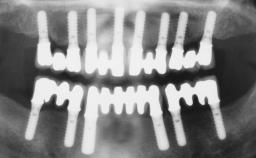

# of Implants 3

Bone Augmentation Horizontal|Staged|Vertical

Augmentation Materials Autogenous chips|Autogenous block(s)